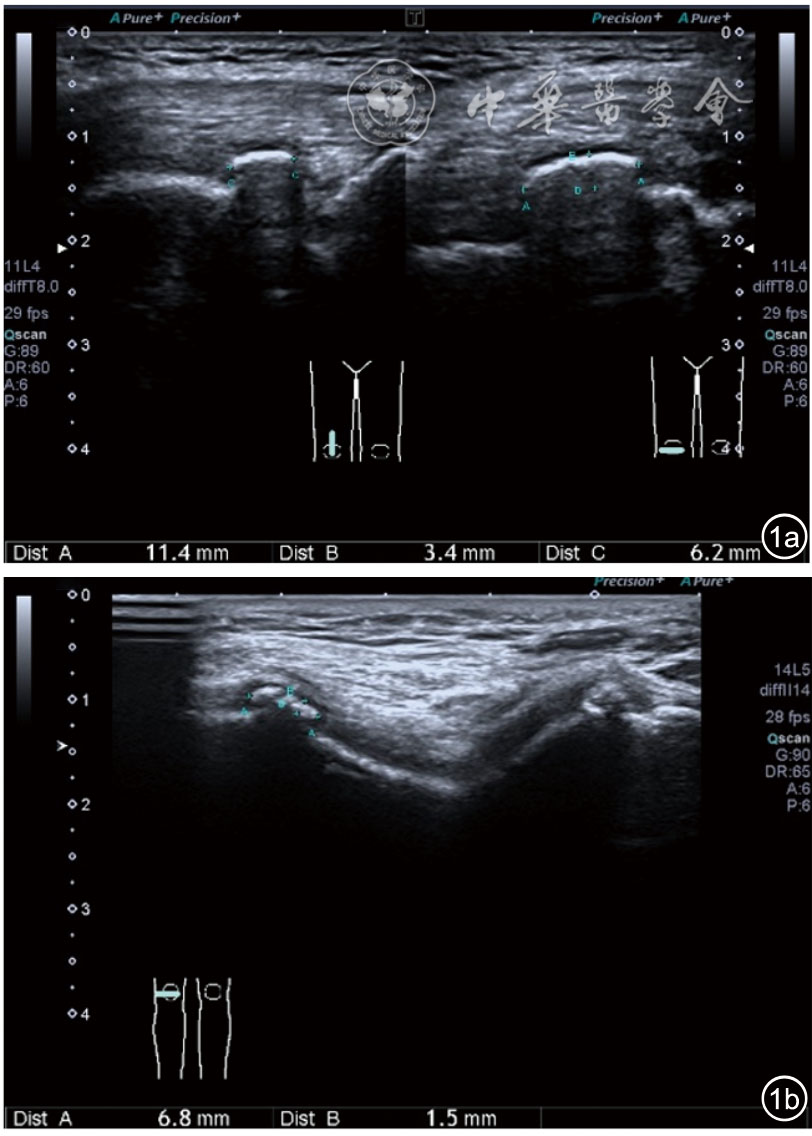

2.关节外表现。(1)副韧带损伤。内侧、外侧均可出现,但是内侧更常见。与膝内翻发生率高有关。超声可见副韧带增厚,回声不均匀,血流增加。半月板突出时可见韧带凸起移位(图7)。(2)髌韧带损伤。可见髌韧带增厚,回声低,有时合并髌下滑囊积液。个别止点处有钙化(图8)。(3)囊肿形成。多见腘窝囊肿,也称Baker囊肿,横切面显示囊肿的颈部位于腓肠肌内侧头与半膜肌腱之间,囊肿大小不一,慢性期可见分隔(图9)。

图9 囊肿形成、囊内可见分隔超声图像